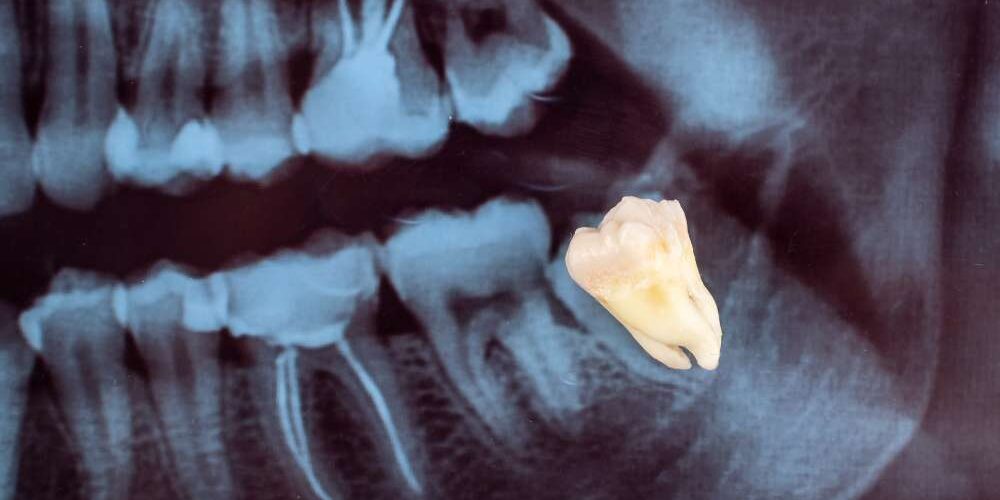

Wisdom tooth extraction can range from a simple procedure to a more complex surgery, depending on the position and condition of your teeth. If your wisdom teeth are impacted, meaning they are trapped beneath the gums or in a tricky position, the surgery may be more involved and require a longer recovery time. Conversely, if the teeth have already erupted and are in a favorable position, the procedure might be quicker and less invasive.